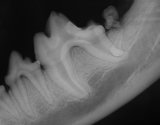

Xray showing buried molar

Pre-op xray to determine condition of first and second molars. Second molar is abnormal. Third molar is present but impacted.